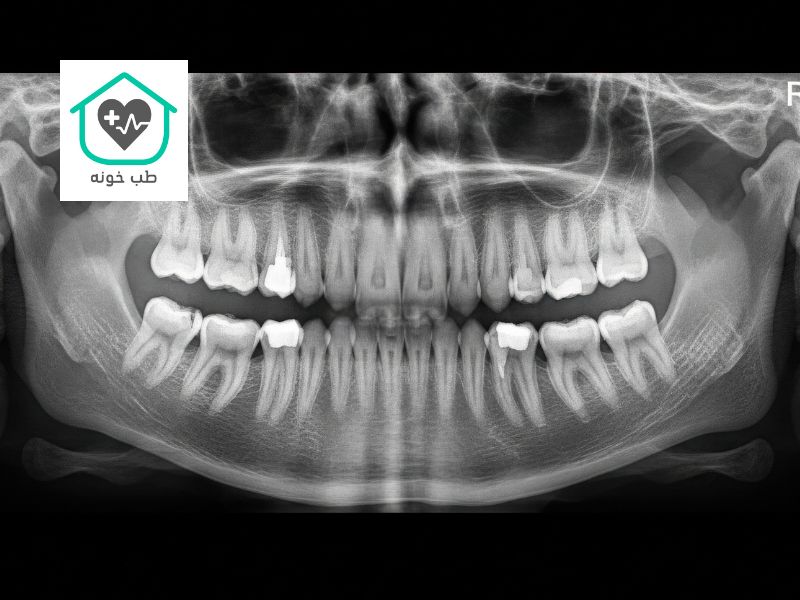

عکس او پی جی دندان (مخفف Orthopantomogram) را میتوان به عنوان عکس پانورامای ۳۶۰ درجه از کل دهان شما تشبیه کرد. این تصویر دو بعدی، یک نمای کلی و پیوسته از تمام دندانهای بالا و پایین، استخوانهای فک، مفاصل گیجگاهی-فکی (TMJ) و حتی بخشهایی از سینوسها را در یک قاب واحد نشان میدهد. به همین دلیل است که بسیاری از مردم به آن عکس دندان کامل انسان میگویند. این عکس، اولین و مهمترین نقشه راه برای دندانپزشک شما در یک معاینه جامع است.

کاربردهای اصلی عکس OPG:

- چکاپ کامل دندانپزشکی؛ اولین قدم در یک معاینه جامع برای بیماران جدید

- بررسی دندانهای عقل؛ بهترین ابزار برای دیدن موقعیت، زاویه و وضعیت دندانهای عقل نهفته

- ارزیابی کلی برای درمانهای پروتزی مانند برنامهریزی برای ساخت یک پروتز ثابت دندان

- بررسی مشکلات مفصل فک (TMJ) مانند درد، صدا یا محدودیت در باز کردن دهان

- تشخیص شکستگیهای فک ناشی از ضربه و حوادث

عکس او پی جی دندان یک ابزار تشخیصی فوقالعاده کارآمد است که با یک بار تابش اشعه، اطلاعات بسیار زیادی را در اختیار دندانپزشک قرار میدهد.